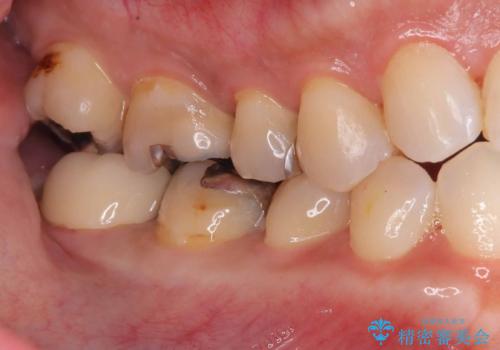

- 銀歯と歯の間に穴があり虫歯になっていました。

銀歯と虫歯を除去後、オールセラミッククラウンで治療を行いました。

銀歯のほとんどは錆びる金属で出来ています。

銀歯を外すと大小様々ですが、そのほとんどが虫歯になっていることが多いです。

今回も虫歯は大きく神経の近くまで広がっていましたが、神経は取らずに治療を終えることが出来ました。